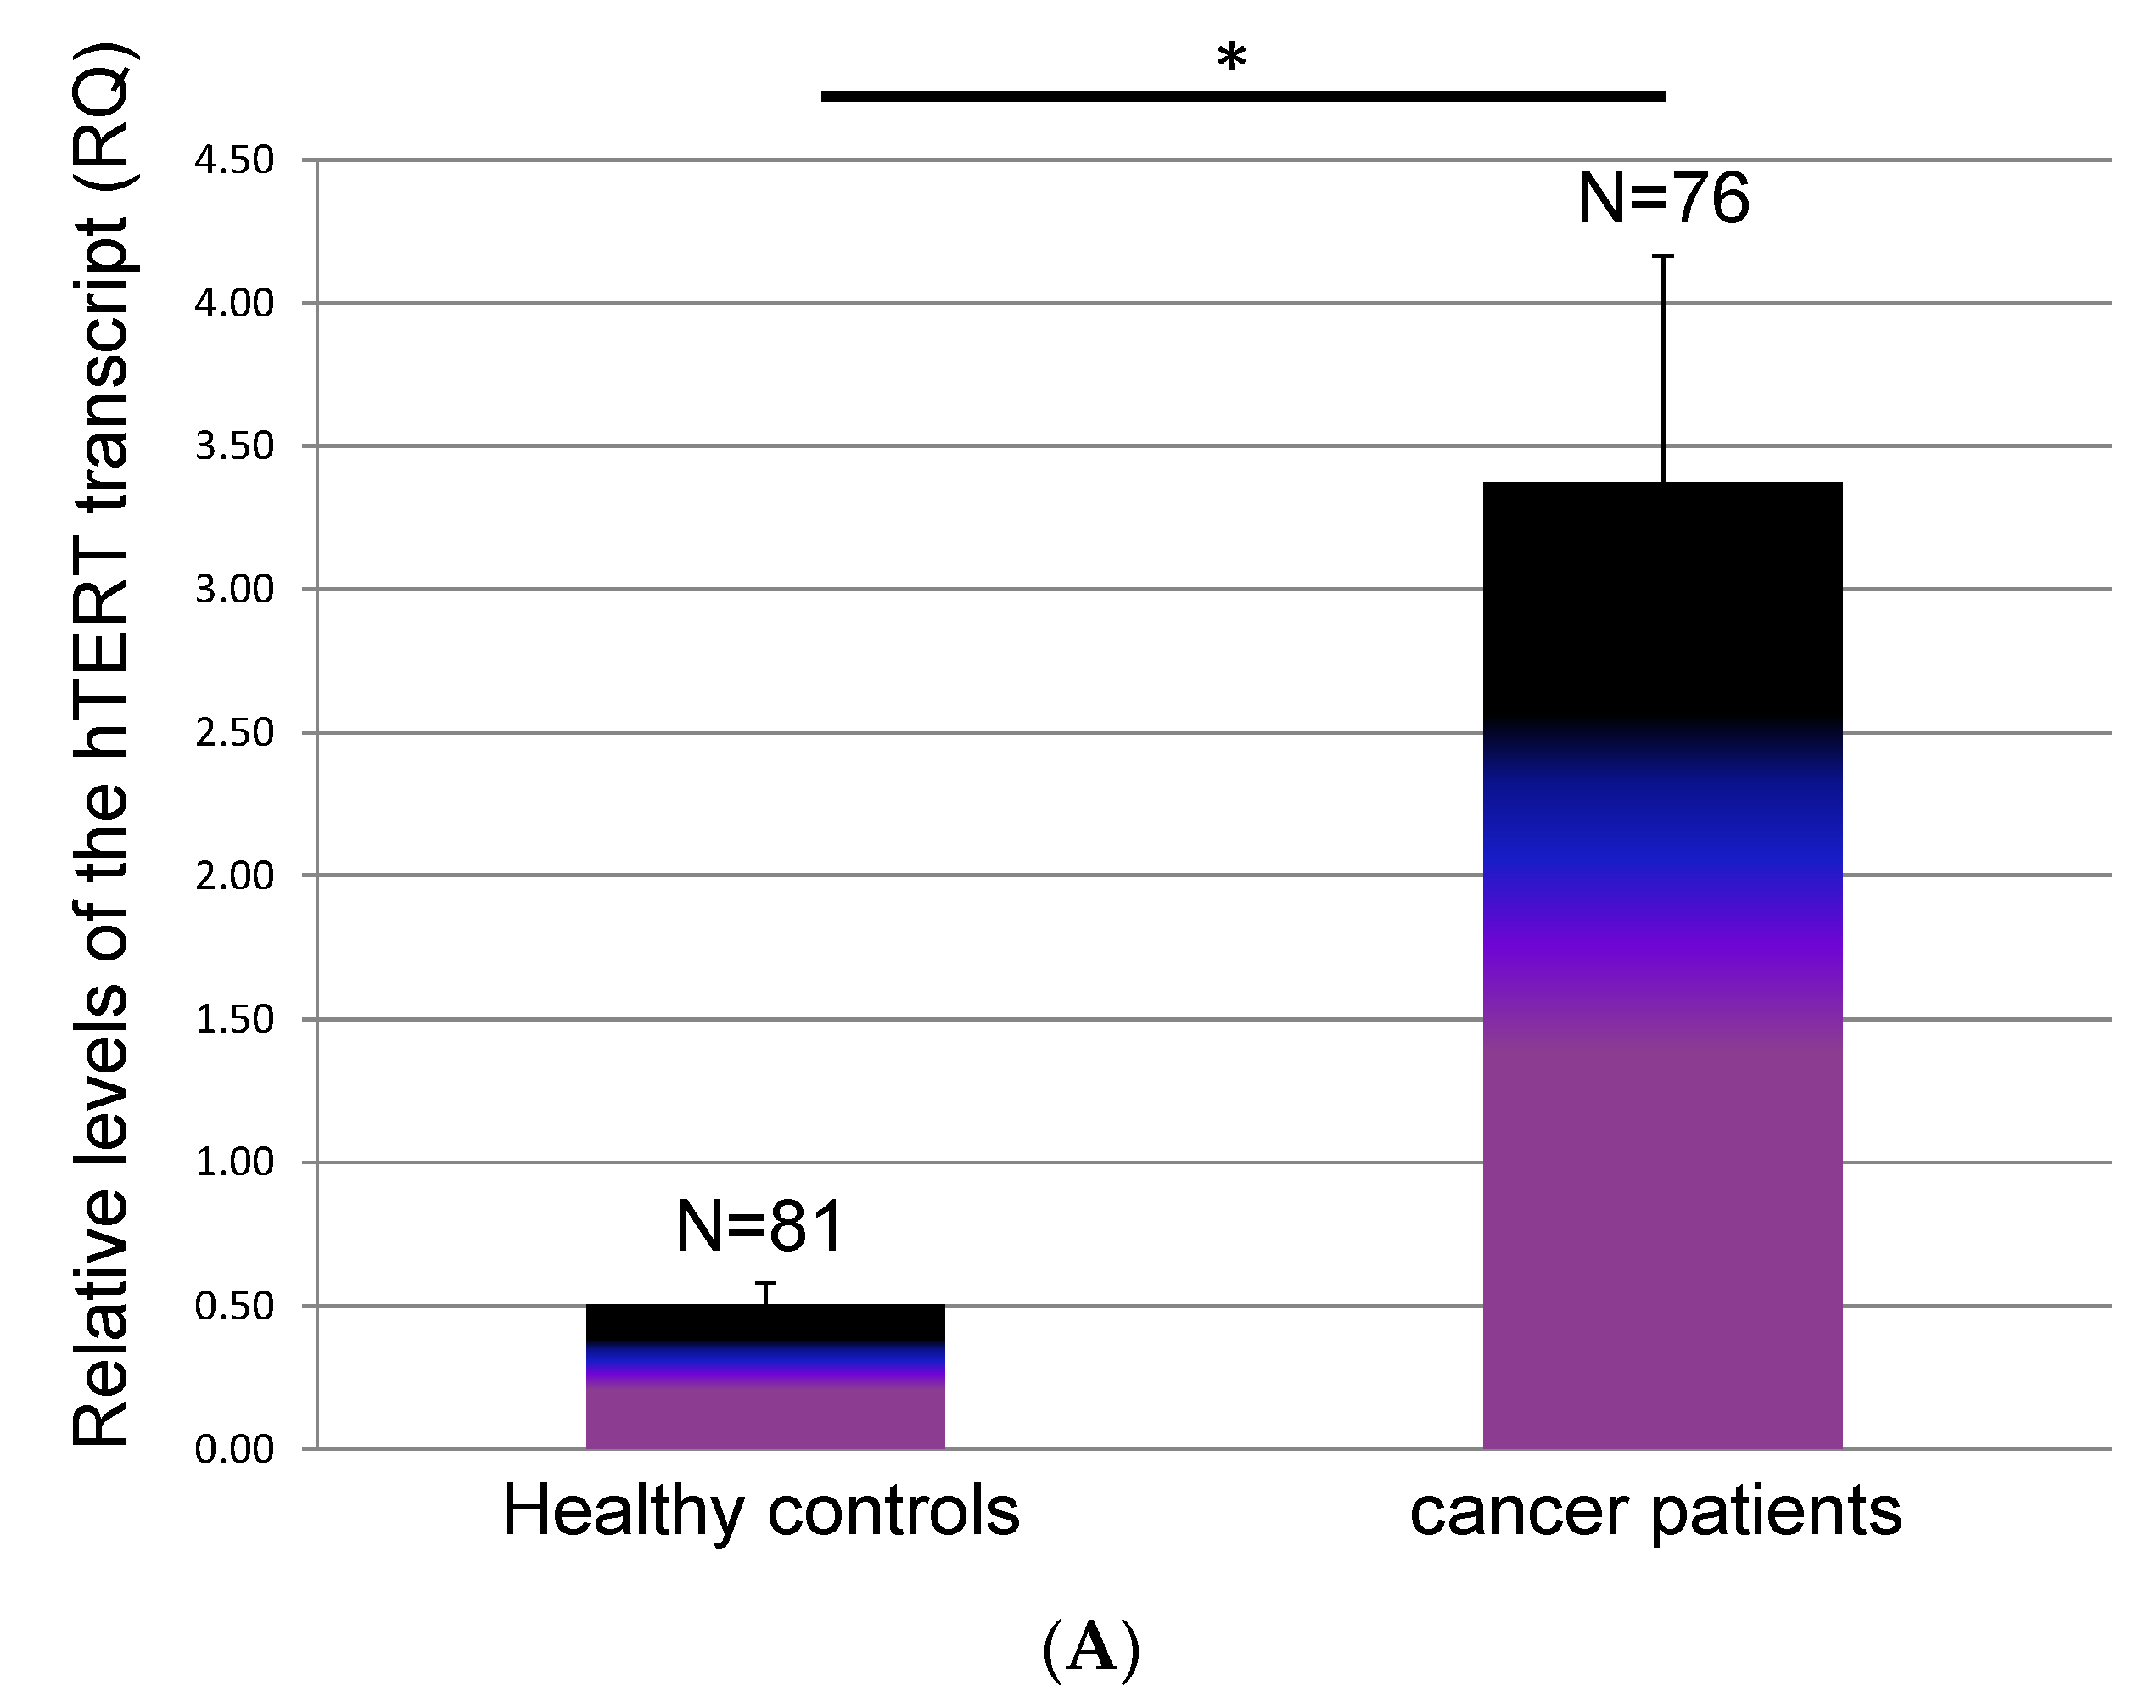

3.3. The Dynamics of hTERT at Time of Evaluation Regarding the Status of Metastasis